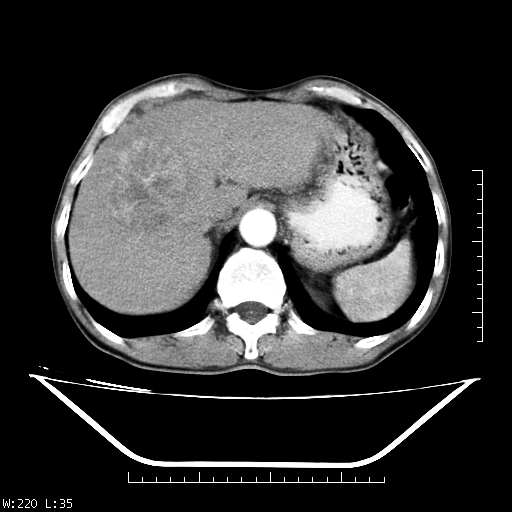

男,70,右上腹痛两月,有乙肝病史,b超提示肝占位,ct如下,请会诊。

补充:该患者afp9.24

肝右叶类圆型密度减低影,密度不均,边界清晰其内可见更低密度影,腹膜后可见小淋巴结肿大,增强扫描动脉期病灶明显强化,静脉期及延时扫描见强化不明显,快进快出表现。

1.肝右叶低密度影考虑为肝癌;

2.肝转移待除外。

平扫呈低密度占位,动脉期斑片状明显强化,病灶边缘清晰,见假包膜;门脉期呈低密度,符合肝癌快进快出强化特征

补充:该患者afp 9.24,似乎与原发性肝癌不符合,另胰头区结构正常吗?请大家继续发表高见。